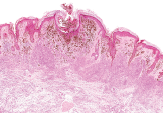

Founded in 1984, DCL Pathology is a College of American Pathologists (CAP) accredited laboratory and is internationally recognized as expert providers of clinical trial pathology services, with specific expertise in women’s health, urology, and oncology studies. The Pathology facility operates in Carmel, Indianapolis, US, and is joining the collective network of Eurofins Clinical Trial Solutions facilities to enhance its service offerings, including providing histology, cytology, pathology, and molecular testing services such as DNA, RNA and Protein quantification, qPCR, and Next Generation Sequencing.